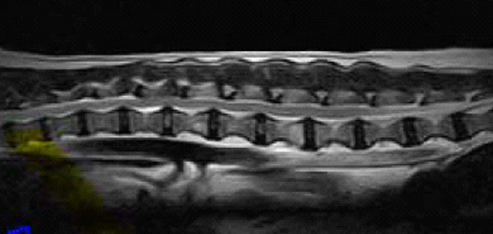

【画像診断】~ダックスフンド、雄10歳、グレート3の椎間板ヘルニア~

▲MRIのT2強調の矢状断面(キャミックに依頼)

▲椎間板ヘルニアがあるMRI像、冠状断像T13-L1の造影なしのT2強調画像、T2強調の矢状断面(キャミックに依頼)

▲犬のほぼ正常な椎間板のMRI像(キャミックに依頼)